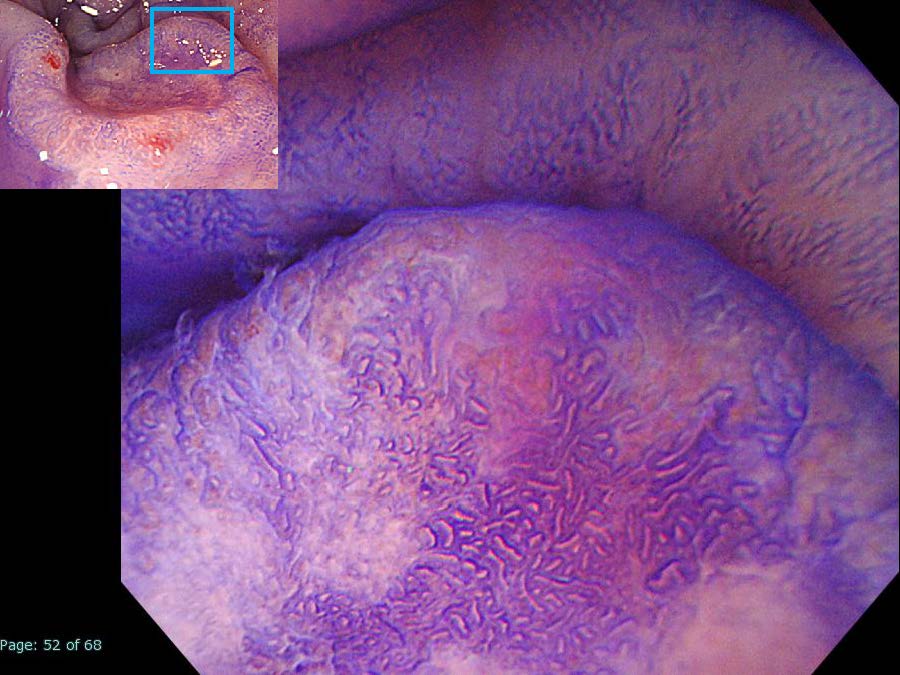

消化管Mapping~大腸~ 2021.10.27

消化管Mapping~大腸~

消化管Mapping

全ページPDFのダウンロードはこちら